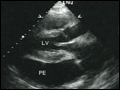

| Figure 229-3 Two-dimensional echocardiographic still-frame image of a patient with a pericardial effusion. Pericardial effusion (PE) is shown as black echo-free space surrounding the heart. LV, left ventricle. | |

view large |